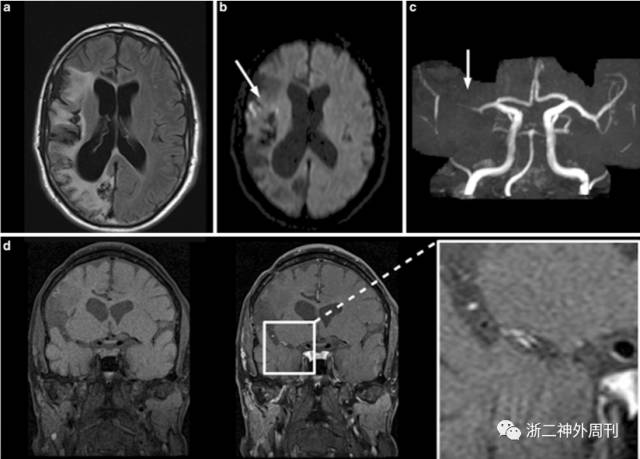

中枢神经系统血管炎引起脑血管壁出现纤维素样坏死、炎性细胞浸润以及管腔内血栓形成,导致脑组织出现梗塞或出血。诊断主要依靠组织活检(图9)和血管造影(图10)[10,11]。

图10. 中枢神经系统血管炎的MRI和MRA表现:A)在右大脑中、后动脉区域显示亚急性缺血等老年缺血性病变(弥散加权成像:B,白色箭头);C)MRA显示右侧大脑中动脉闭塞;D)相应的血管壁强化。